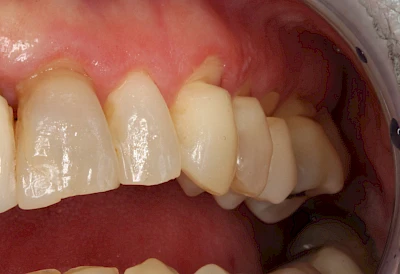

Auswaschung (Erosion) dagegen ist eine Verschleißerscheinung der Zähne aufgrund von immer wiederkehrenden Säureangriffen durch die Nahrung, verstärkt zum Beispiel durch den Genuss säurehaltiger Getränke oder Speisen. Auch bei Menschen mit einer Essstörung (z. B. Bulimie) können die Zähne durch die Magensäure ausgewaschen erscheinen.

Eine Sonderform sind sogenannte keilförmige Defekte im Bereich der Zahnhälse. Hier geht man davon aus, dass Knirschen und Pressen in Kombination mit falschen Putzgewohnheiten (zu hoher Putzdruck, Verwendung von Zahnpasta mit hohen Abrasionswerten) eine Rolle spielen.